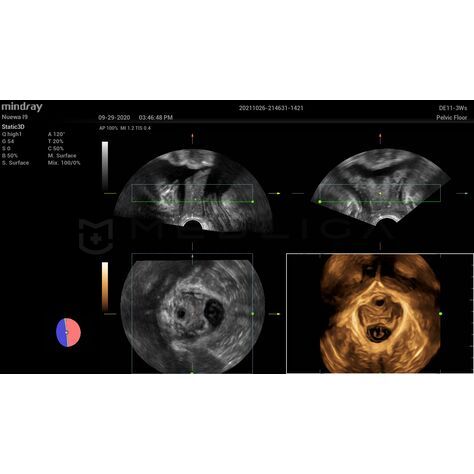

Smart Pelvic - новое решение, позволяющее значительно упростить диагностическую процедуру и свести к минимуму время исследования функций мышц тазового дна. Благодаря чрезвычайно простому пользовательскому интерфейсу, программа генерирует стандартную систему координат и автоматически просчитывает все связанные измерения в течение нескольких секунд.